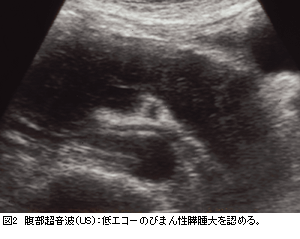

内視鏡的逆行性膵管造影(ERP)における細くて壁の不整像を伴う膵管狭細像(図1)と膵腫大(図2)は本症に特徴的である。典型例では“ソーセージ様”のびまん性の膵腫大を呈するが,限局性腫大を呈する例では膵癌との鑑...